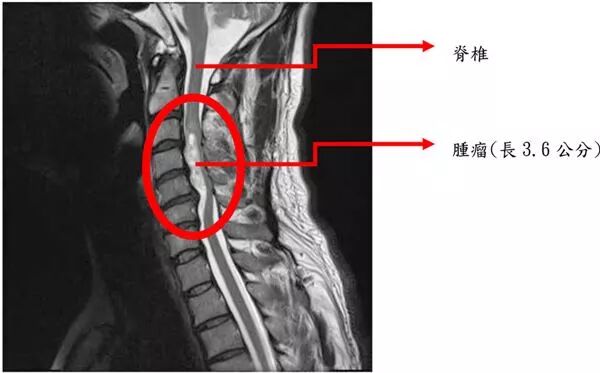

曾有一个名为吉姆·加斯的美国人,前往墨西哥和阿根廷的干细胞诊所治疗中风,结果,他的脊柱上,长出了一个大肿瘤!

癌细胞来自他人;